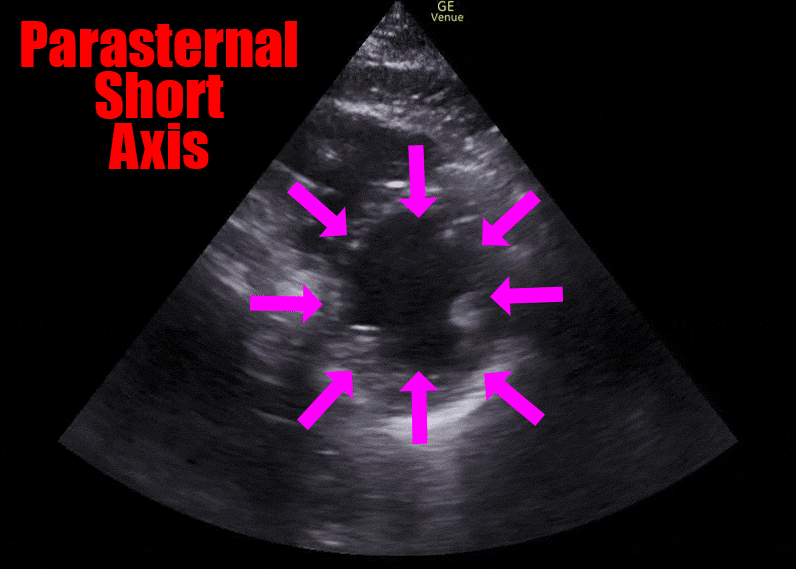

The ECG shows ST segment elevation in the anterior leads, and the ultrasound shows an akinetic segment in the distribution of the LAD. This is the regional wall motion abnormality. The image below illustrates the finding. The heart cath confirmed a total occlusion of the LAD.